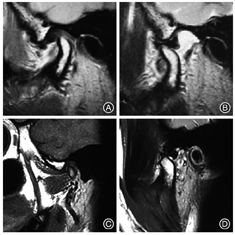

广州医科大学附属口腔医院颞下颌关节病科通过3万余例TMD患者临床诊疗经验,提出了"序列化、微创化、数字化、舒适化、人文化"的特色诊疗模式[4]。第一阶段为保守治疗,具体治疗方案是关节腔注射治疗(关节腔内注射透明质酸钠,图2)联合关节咬合板治疗,再辅以理疗、药物治疗和手法复位,有效率达85%左右,是TMD患者选择最多也是最佳的"一线"治疗方法。少数患者对于保守治疗效果不佳,如疼痛、绞锁、开口限制未得到改善,笔者团队会建议患者进行第二阶段治疗,即关节镜微创治疗(图3),这可进一步提供辅助诊断以及治疗作用。关节镜治疗可对病变关节进行灌洗、黏连松解、清除黏连物、骨组织修整以及关节盘复位,此法对于保守治疗无效的TMD患者有肯定的疗效。第三阶段为开放性手术(图4),因颞下颌关节盘前移位导致长时间疼痛和功能障碍,因外伤、关节盘前移位及骨关节病导致的关节盘穿孔,或颞下颌关节镜微创治疗疗效不佳并愿意接受此法的患者,施行颞下颌关节盘复位锚固术或关节盘穿孔修补术。本文重点阐述"序列梯度"治疗中"保守治疗"的一种临床治疗方法——"颞下颌关节咬合板"治疗。